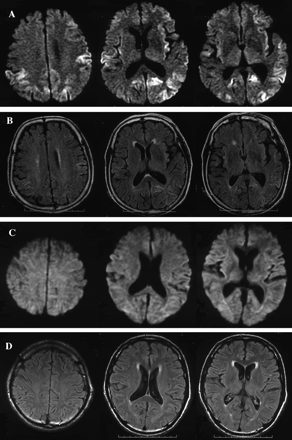

图1所示。大脑核磁共振在16个月后病人2 (A, B)和病人8在7个月后开始(C, D)。A和C是diffusion-weighted成像(驾车),和B和D是fluid-attenuated反转恢复(天赋)成像。在病人2中,酒后驾驶显示hyperintense信号双边额,顶叶、枕叶皮层(A),和天赋成像还显示轻微hyperintensity信号在大脑皮层驾车病变(B)。在病人8中,醉酒驾车和天赋大脑成像显示没有明显的异常信号(C, D)。

神经系统检查4个月后开始显示含糊不清构音障碍,左侧上、下肢的笨拙,痴呆。EEG是正常的。14-3-3蛋白的CSF水平是模棱两可的。MRI显示gyriform hyperintensity双边额、颞、顶叶、枕叶皮质醉酒驾车。正的大脑显示弥漫性双边丘脑皮层代谢减退。库贾氏症被怀疑作为早期诊断。

患者1和2的平方毫米皮质出现迟发性的形式,慢慢进步的痴呆(表1)。PSWCs脑电图缺席在早期阶段(表2)。这些特性与之前报道的平方毫米皮质病例。3病人没有完成的临床标准sCJD因为缺乏临床症状。20.重要的是,大脑皮层hyperintensity信号驾车(见表2已报告),这为诊断sCJD是有用的,19日,22日,23日很容易使我们可能库贾氏症的诊断。基底节和丘脑在这些情况下没有hyperintensity核磁共振信号。CSF水平增加(见14-3-3蛋白支持诊断表2)。平方毫米皮质形式经常显示缓慢进行性痴呆没有其他神经系统异常,广告和痴呆与征收机构对鉴别诊断很重要。皮质hyperintensity信号在急性缺血性中风的醉酒驾车被发现,23单纯疱疹脑膜脑炎,22、23创伤后挫伤,22、23postictal变化,22和米拉(线粒体肌病、脑病、乳酸酸中毒和类似中风发作)24;然而,他们并没有观察到广告25或者和路易体痴呆。19我们建议以下为平方毫米皮质sCJD诊断标准:1)进行性痴呆,2)皮质hyperintensity信号在酒后驾驶,和3)脑脊液14-3-3蛋白质含量增加,排斥其他痴呆症,包括其他类型的朊病毒疾病。其他神经精神异常比痴呆或PSWCs脑电图不一定是必需的。

平方毫米的情况下丘脑的形式,发病年龄范围从30到71年,临床过程的持续时间从13到73个月(见表1)。临床表现包括精神病症状,痴呆,小脑性共济失调、失眠、和自主失败(见表1)。至于FFI的突出特点和SFI,失眠在只有一个病人(病人4),和自主症状被发现在三个病人(病人4、5、7)。脑电图显示没有PSWCs除了一位病人(病人6)显示PSWCs很晚阶段(见表2)。这些特性与先前报道的患者数目丘脑3或者你以后。8、10脑部核磁共振成像,包括醉酒驾车,几乎是正常的平方毫米丘脑的患者除了脑萎缩或白质后期的变化(见表2)。这些功能与以前的报道相一致SFI患者。8、10在我们的研究中,两个病人检测CSF 14-3-3蛋白,一个是积极的,另一个是模棱两可(见表2)。在文献中,据我们所知,有报道称,4平方毫米丘脑sCJD患者检查脑脊液14-3-3蛋白:考试是积极的6和负三。7、8考虑这些报道与我们的结果,我们不能得出结论,CSF 14-3-3蛋白诊断平方毫米丘脑sCJD足够敏感。最初的临床诊断,进行性核上的麻痹(PSP),脊髓小脑的变性(SCD),或广告一直怀疑(见表1),表示相当困难的临床诊断平方毫米丘脑的形式。然而,我们回顾CBF-SPECT研究显示特征的结果减少CBF的双边丘脑和大脑皮层的相对早期阶段(见表2)。在以前的报告CBF-SPECT研究库贾氏症病人,减少CBF的目视检查发现大脑皮层不同区域的但不是在丘脑。26日,27日没有关于CBF-SPECT平方毫米丘脑sCJD报告。在摄影的研究中,丘脑和大脑皮层的代谢减退患者SFI报道10或者在某些FFI患者。28、29CBF和丘脑葡萄糖代谢相对保存在广告。30.在PSP,显著减少葡萄糖代谢不是丘脑中发现,而是在额叶皮层通过地区检测到/枕的代谢率。31日多系统萎缩,零星的SCD的表型,减少丘脑CBF的报道;然而,显著减少CBF还检测到的背壳。32我们的患者数目丘脑sCJD没有CBF的壳(见减少图2 b)。我们的研究结果清楚地表明,减少双边丘脑CBF以及代谢减退,与他们的保护壳,将是一个特别有用的诊断为平方毫米丘脑sCJD标记。

有趣的是,在病人与平方毫米(corticothalamic)形式(病人3)相结合,两平方毫米的神经影像学研究显示功能皮层和丘脑的形式,也就是说,hyperintense信号在醉酒驾车和丘脑皮层代谢减退摄影(见表2),与这个病人的病理结果一致。

结果:8例病理分为皮质(n = 2)、丘脑(n = 5),并结合(corticothalamic) (n = 1)的形式。皮质的形式被迟发性的特点,慢慢进步的痴呆,皮质hyperintensity信号diffusion-weighted大脑成像(驾车),和CSF 14-3-3蛋白水平升高。丘脑的形式显示各种神经系统症状包括痴呆、共济失调,锥体和锥体束外的迹象出现在各种年龄和疾病持续时间相对较长。脑电图特点和MRI异常几乎缺席。然而,所有四个患者对脑血流量(CBF)研究使用SPECT显示减少的CBF丘脑和大脑皮层。合并后的表单功能的皮层和丘脑的形式,显示皮质hyperintensity信号醉酒驾车和丘脑的代谢减退18F] 2-fluoro-2-deoxy-d-glucose宠物。

结论:MM2-type零星的克雅氏病的临床诊断疾病,皮质hyperintensity diffusion-weighted MRI信号是有用的皮质形式和丘脑的低灌注或代谢减退脑血流量SPECT或[18F] 2-fluoro-2-deoxy-d-glucose宠物的丘脑的形式。